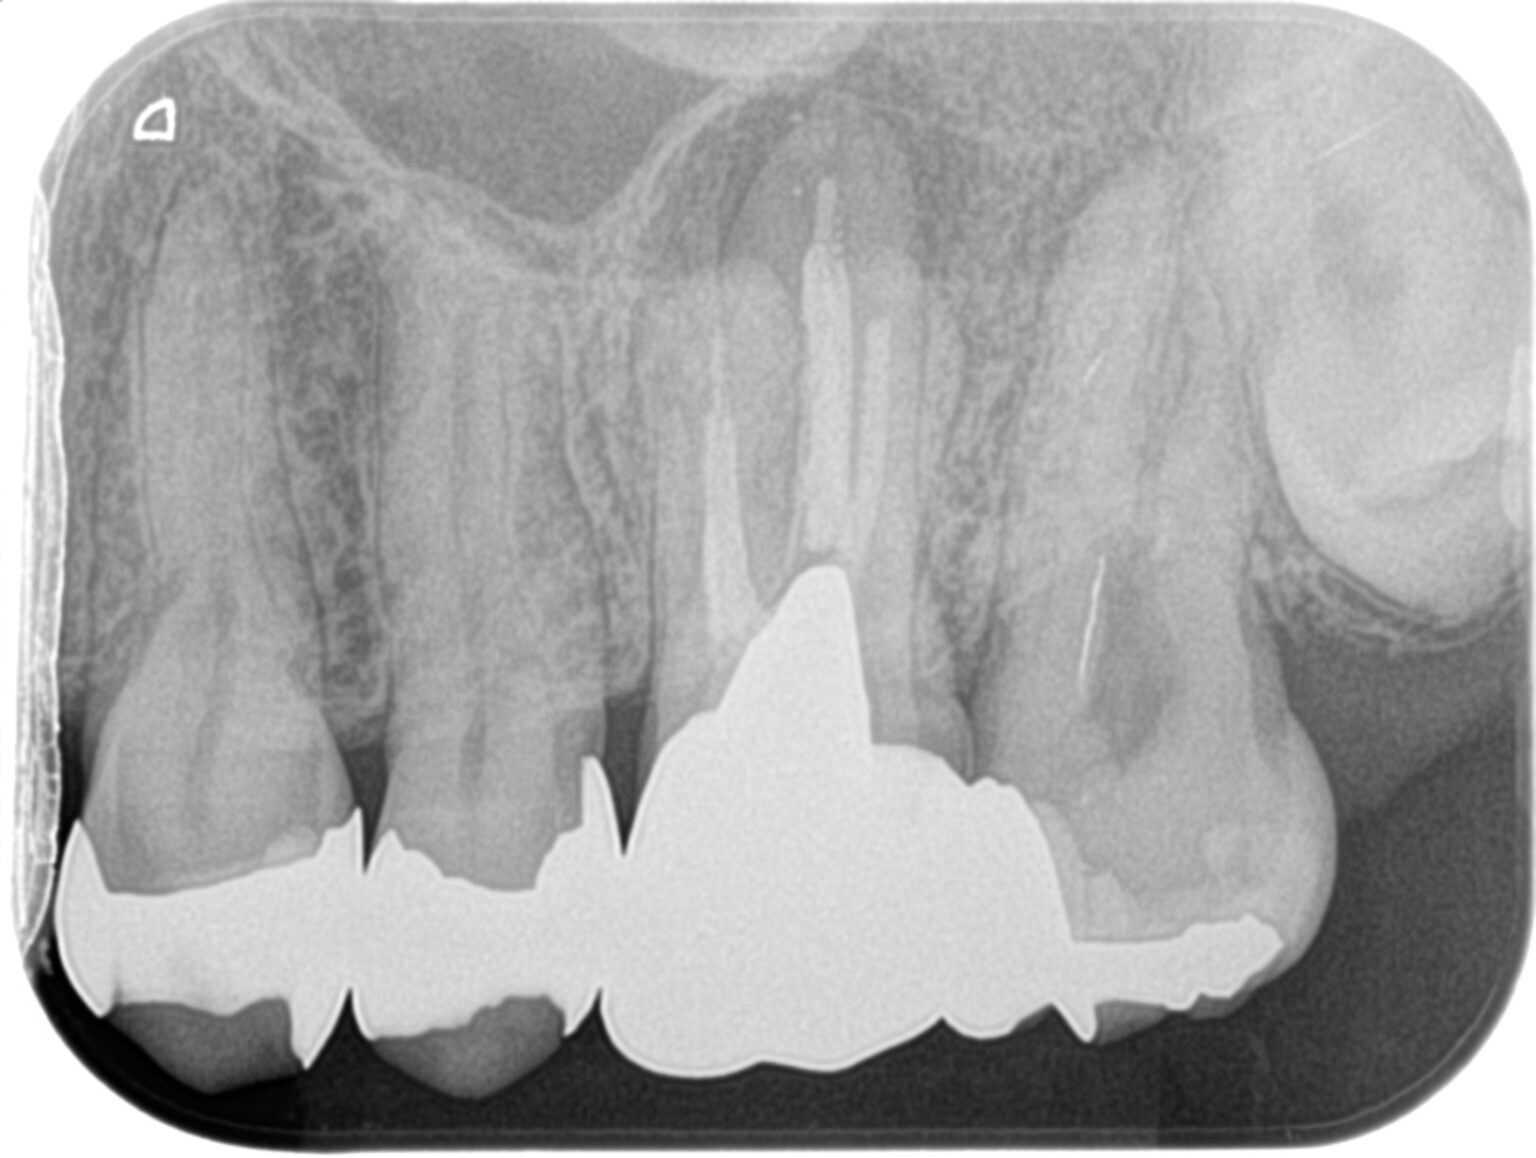

Apico-Marginal Defectを人為的に作成すると…〜#14 Intentional Replantationとその1yr recall

紹介患者さんの治療とその1年予後。 以前の記事で口蓋の皮質骨が再生されているCaseがあった。 人為的に壊さなければ歯槽骨は回復する〜#13 Intentional Replantation 6M recall 口蓋の皮 … 続きを読む Apico-Marginal Defectを人為的に作成すると…〜#14 Intentional Replantationとその1yr recall